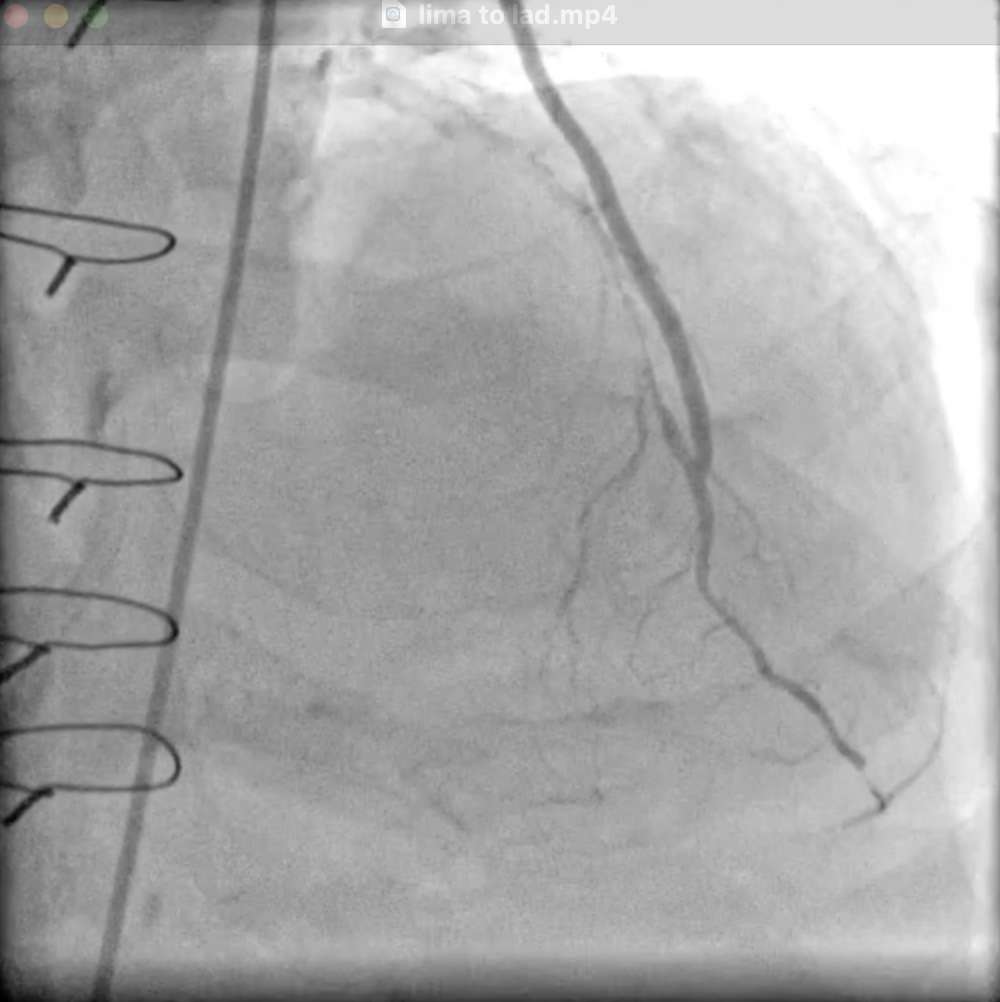

LMCA occluded from the ostium. LAD - ostioproximal occlusion. LCX - ostioproximal occlusion. RCA-dominant, stent with ISR 90%. LIMA to LAD patent, flows well. SVG to D1 and PDA diagonal occluded.

lima to lad.mp4